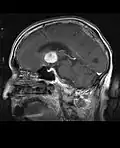

• MRI significantly underestimates extent of involvement; May appear focal on CT or MRI but parenchyma is typically diffusely involved.

• Intensely enhancing on MRI; may have a diffuse or “cotton wool” appearance on imaging.